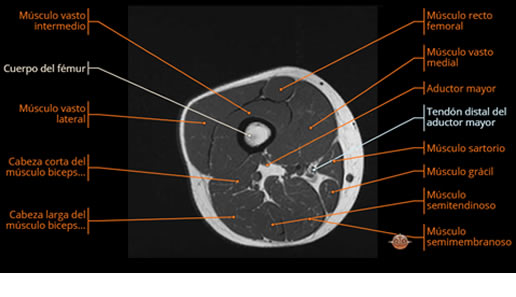

Se realiza estudio de MRI de muslo izquierdo en diferentes planos, con secuencias de Spin Echo, GRE; ponderadas a T1 y a T2, se utilizan pulsos de saturación de grasa y se administra medio de contraste IV a base de Gadolinio en base al peso del paciente.

La diáfisis femoral izquierda muestra reacción perióstica importante, se extiende desde el cuello del fémur, invade trocánteres, diáfisis femoral, medial y distal, es compatible con un proceso infeccioso óseo, el complejo muscular del muslo se ve edematizado.

Desde el punto de vista patológico, el tumor suele localizarse en la diáfisis de huesos largos (como fémur, tibia o húmero), pero también puede afectar costillas, pelvis y columna vertebral. A medida que la lesión progresa, se produce destrucción ósea, formación de tejido blando tumoral y reacción perióstica característica.

La resonancia es la modalidad de elección para valorar la extensión intramedular y la infiltración en tejidos blandos, brindando una imagen más detallada del compromiso tumoral. Los hallazgos característicos incluyen:

Compromiso de la médula ósea adyacente y de estructuras vecinas, como músculos y neurovasculatura.